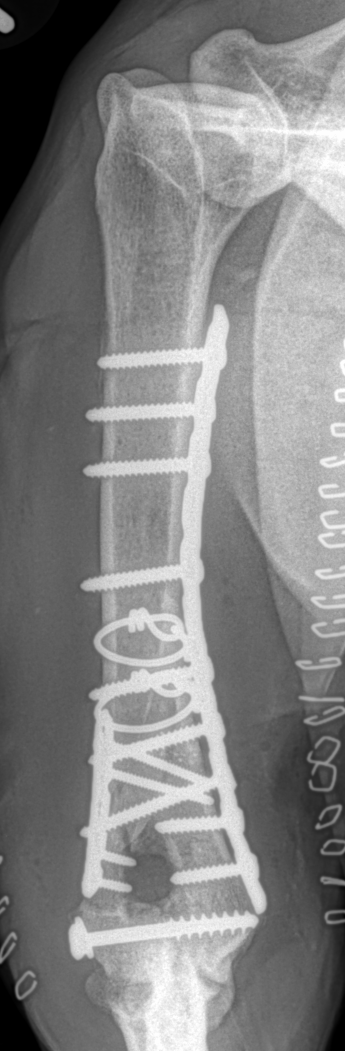

Multiple bone plates, screws and cerclage wires may be used to stabilize fractures. This common - and very complex - injury is often described as a "T" or "Y" fracture of the humerus and results in three separate segments including an intra-articular component. The joint surface is reconstructed first followed by application of bone plates both medially and laterally in neutralization.